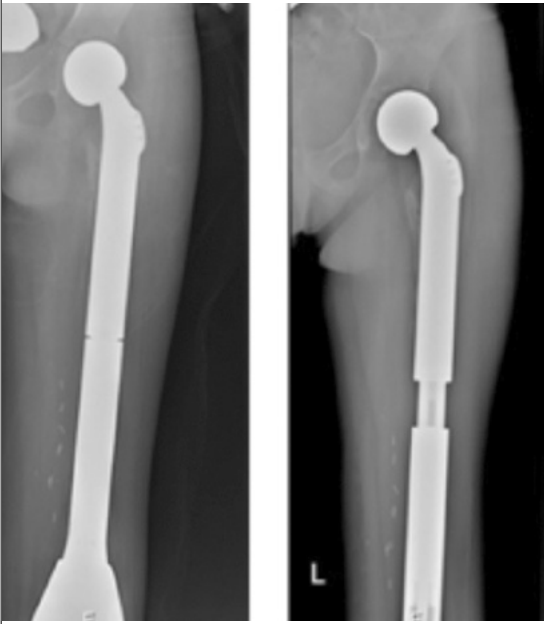

באופן טבעי, במקביל לשינוי המגמה לכיוון ניתוחים משמרי גף, עלתה חשיבות השחזור של חסר הרקמה אשר נותר אחרי הכריתה של הגידול. חלקו השחזורי של הניתוח הוא במידה רבה מורכב יותר בילדים מאשר במבוגרים. בעוד שבמבוגרים, במרבית מקרי הממאירות בעצמות הארוכות של הגפיים אפשר לבצע שחזור בעזרת משתל, אשר מחליף את מקטע העצם שנכרת, בילדים, משתל רגיל אינו מתאים, בגלל הצמיחה הצפויה בגף הנגדי. הצורך לשמור על שוויון באורך הגפיים, בין הגף המנותח לגף הנגדי, כאשר הגף הבריא של הילד ימשיך לצמוח בממדיו, מחייב פתרון אחר.

אחד החידושים בתחום הטיפול הניתוחי בממאירויות גרמיות בילדים, הוא שימוש במשתלים מתארכים. המשתלים המתארכים הראשונים הצריכו ניתוחים רבים לשם ביצוע הארכות חוזרות של המשתל. עם העלייה במספר הניתוחים, גדל גם הסיכון לסיבוכים. ישנה אפשרות לשימוש במשתלים הניתנים להארכה באופן לא ניתוחי, בעיקר באמצעות שדה מגנטי חיצוני.